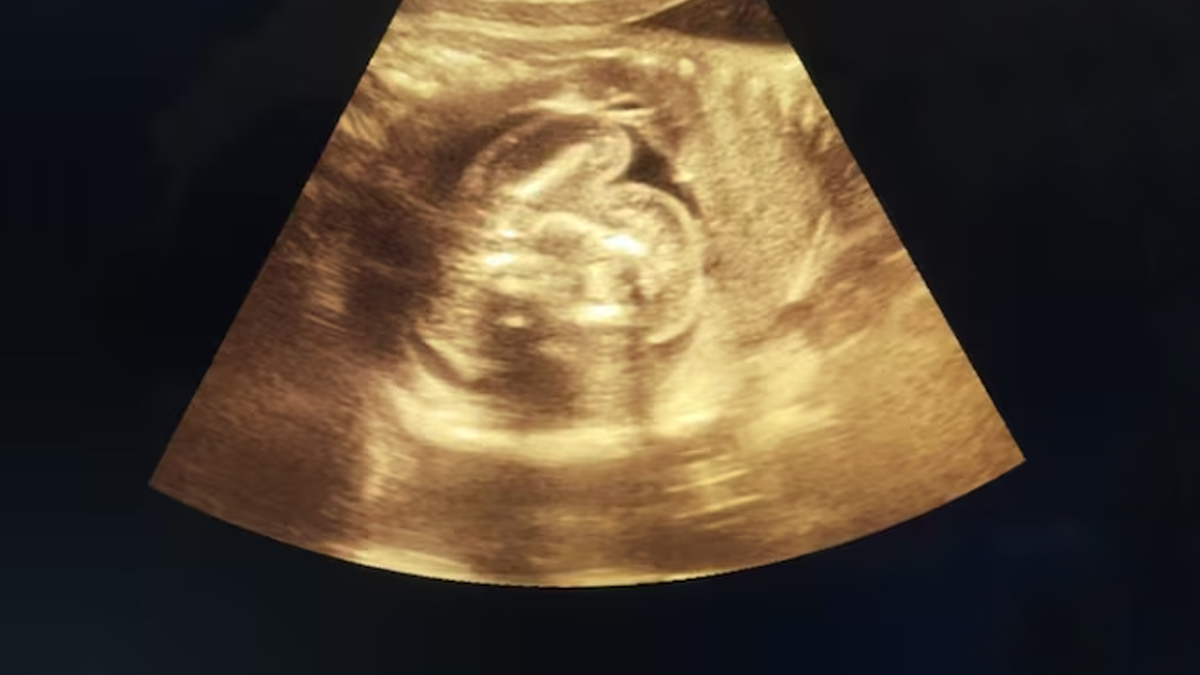

मेडिकल साइंस में कई रहस्यमयी और दुर्लभ स्थितियां देखने को मिलती हैं, लेकिन हाल ही में महाराष्ट्र में सामने आया एक मामला डॉक्टरों के लिए भी किसी आश्चर्य से कम नहीं था। सोनोग्राफी के दौरान एक नवजात शिशु के पेट में भ्रूण पाया गया, जिसने सभी को हैरान कर दिया। यह स्थिति ‘फीटस इन फीटू’ (Fetus in Fetu) कहलाती है, जो बहुत दुर्लभ है। दुर्लभ जन्मजात विसंगति का पता कुछ दिन पहले चला जब 32 वर्षीय महिला नियमित जांच के लिए बुलढाणा जिला महिला अस्पताल गई। जिस वक्त इस स्थिति का पता चला तब महिला गर्भवस्था के नौवें महीने में थी, जांच के बाद डॉक्टरों ने इलाज शुरू कर दिया। इस लेख में हम जानेंगे फीटस इन फीटू क्या है और इस स्थिति के पीछे छुपे संभव कारण। इस विषय पर बेहतर जानकारी के लिए हमने लखनऊ के डफरिन हॉस्पिटल की वरिष्ठ गाइनोकॉलोजिस्ट डॉ लिलि सिंह से बात की।

इस स्थिति का पता आमतौर पर सोनोग्राफी, सीटी स्कैन या एमआरआई के जरिए चलता है। सोनोग्राफी के दौरान अगर डॉक्टर को पेट में कोई असामान्य हलचल दिखती है, तो वे आगे की जांच करने की सलाह देते हैं।